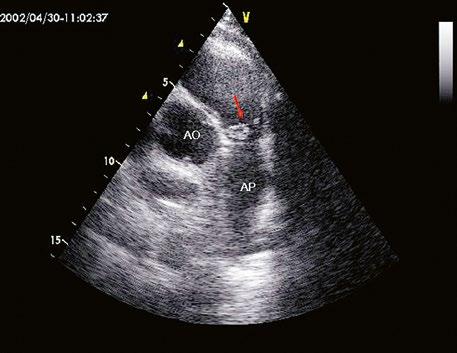

Supravalvární pulmonální stenóza a stenózy větví plicnice bývají součástí komplexních VSV (např. Fallotovy tetralogie) nebo syndromů (Williamsův syndrom, syndrom Noonanové, syndrom vrozené rubeoly, Alagillův syndrom aj.) (Obr. 45.39). Získané stenózy větví plicnice, ale i úplný uzávěr větve plicnice můžeme vidět po spojkových operacích podle BlalockaTaussigové (Obr. 45.40, Obr. 45.41). Pro zobrazení supravalvárních a periferních stenóz plicnice je optimální CT angiografie (Obr. 45.40, Obr. 45.41, Obr. 45.42, Obr. 45.43).

Obr. 45.39 TEE, valvární a supravalvární stenóza plicnice blízko nad chlopní, označena křížky. Valvární stenóza s domingem chlopně označena šipkou. AP – kmen plicnice za stenózou, RVOT – výtokový trakt pravé komory